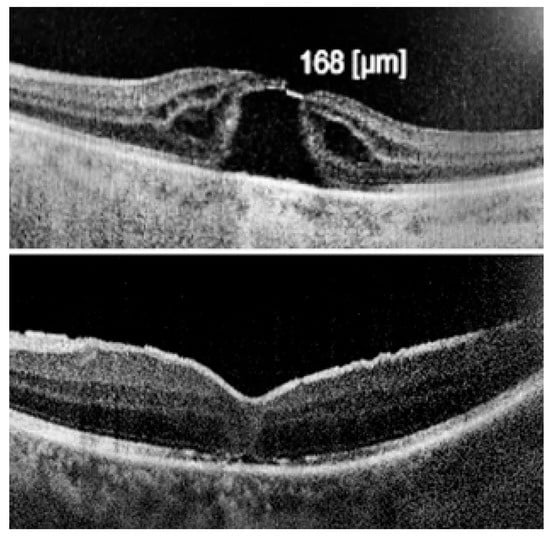

The ILM was peeled without the use of vital dyes, employing visualization techniques for transparent structures. A 25G silicone soft-tip cannula was used to gently approximate the edges of the macular hole under a balanced salt solution. Triamcinolone aceonide (Kenalog) was deposited on the ILM surface to enhance its visibility, and additional guidance was provided by instrument shadows under green-light illumination. Peeling was initiated at the point of weakest adhesion between the ILM and the retina. A pair of vitreoretinal forceps (e.g., Alcon Grieshaber AG, Schaffhausen, Switzerland) was used to gently grasp and lift the ILM to initiate separation. The extent of peeling covered an area of approximately 2–3 optic disc diameters around the hole to relieve tangential traction. Following ILM peeling and centripetal tissue mobilization, the macular hole edges were approximated under balanced salt solution or, in selected cases, perfluorocarbon liquid. Closure was monitored in real time using high-resolution intraoperative OCT (RESCAN™ 700 integrated with OPMI LUMERA® 700 microscope, Carl Zeiss Meditec AG, Jena, Germany). Representative intraoperative OCT images before and after ACP application are presented in Figure 1, Figure 2 and Figure 3.

Figure 1. Intraoperative images before ILM peeling and after macular hole closure, with superficial approximation of the edges using a silicone-tipped cannula.